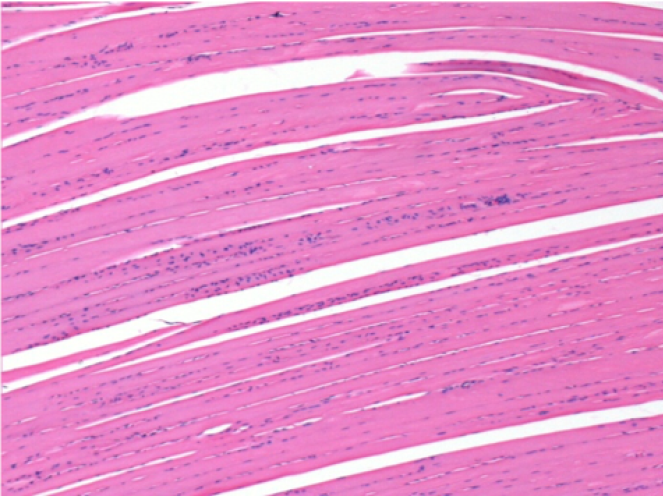

09

7 mesi dopo Iniezione di Endopeel

Scatola Nr 5

7 mesi (Giorno210) dopo iniezione IM di 0.1ml di Endopeel nel muscolo pretibiale destro ( Dx).

Restitutio ad integrum completo dopo 7 mesi

Sx : Controllo-100x-Giorno210

Dx:100x-Giorno210

Sx :Controllo 50x-Giorno210

Dx:50X-Giorno210